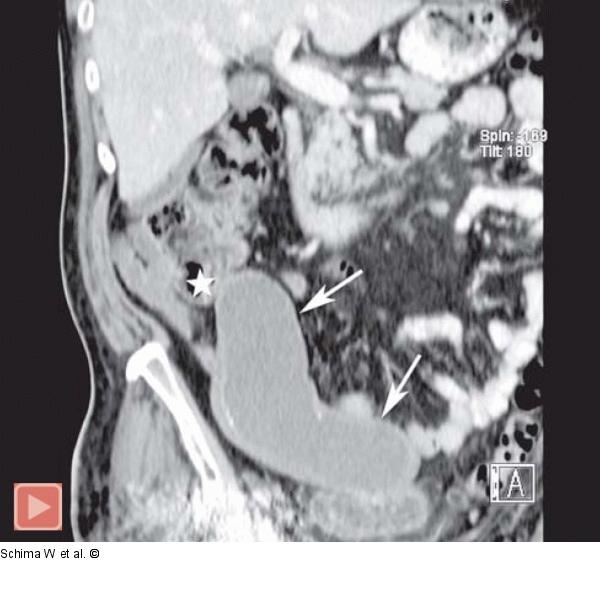

Abbildung 2b: MDCT- 3D-Rekonstruktion Die 3D-Rekonstruktion der MDCT (Curved Planar Reconstruction in parakoronaler Ebene) zeigt anschaulich die gesamte Ausdehnung der tubulären Raumforderung (Pfeile) sowie die Beziehung zum Zökalpol (Stern). Es lässt sich lediglich der liquide (muzinreiche) Inhalt nachweisen, nicht jedoch ein solider Tumor bzw. eine Infiltration in Nachbarorgane. Es findet sich auch kein Hinweis auf eine Ruptur mit Tumorzellverschleppung in die freie Bauchhöhle im Sinne eines Pseudomyxoma peritonei. Am unteren Bildrand finden sich Artefakte aufgrund einer implantierten Hüftprothese rechts. |

Die 3D-Rekonstruktion der MDCT (Curved Planar Reconstruction in parakoronaler Ebene) zeigt anschaulich die gesamte Ausdehnung der tubulären Raumforderung (Pfeile) sowie die Beziehung zum Zökalpol (Stern). Es lässt sich lediglich der liquide (muzinreiche) Inhalt nachweisen, nicht jedoch ein solider Tumor bzw. eine Infiltration in Nachbarorgane. Es findet sich auch kein Hinweis auf eine Ruptur mit Tumorzellverschleppung in die freie Bauchhöhle im Sinne eines Pseudomyxoma peritonei. Am unteren Bildrand finden sich Artefakte aufgrund einer implantierten Hüftprothese rechts. |